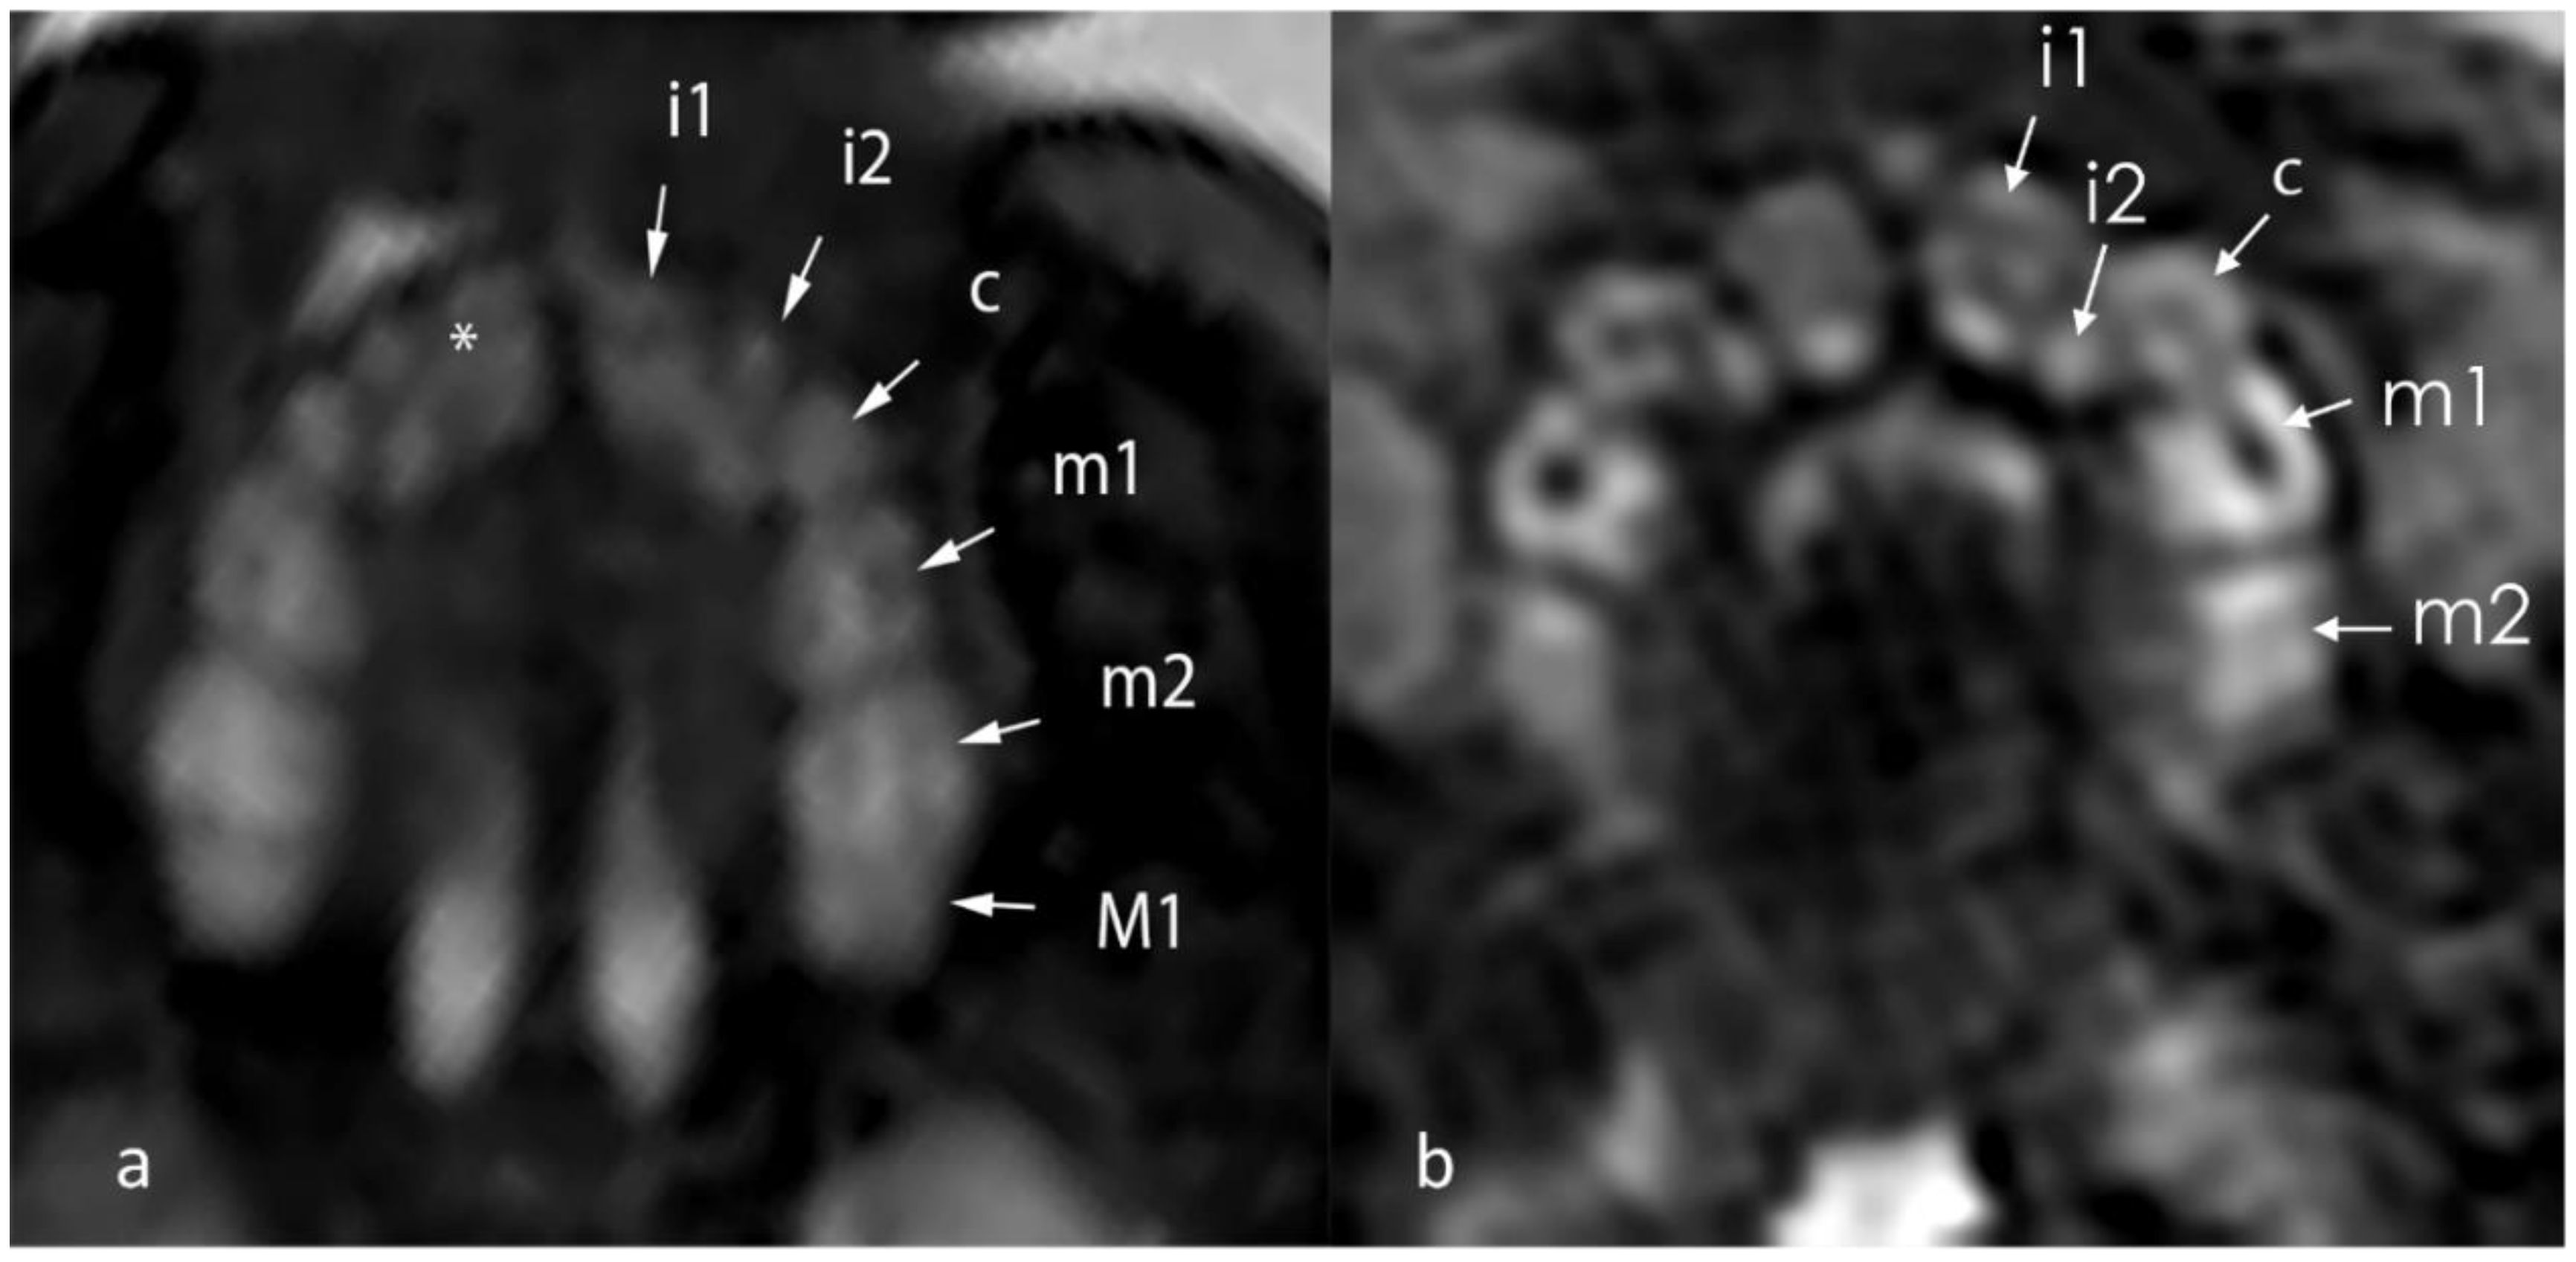

- Seabra, M.; Vaz, P.; Valente, F.; Braga, A.; Felino, A. Two-Dimensional Identification of Fetal Tooth Germs. Cleft Palate Craniofac. J. 2017, 54, 166–169. [Google Scholar] [CrossRef] [PubMed]

- Couly, G.; Nicot, R.; Kverneland, B.; Ferri, J.; Levaillant, J.M. Fetal dental panorama on three-dimensional ultrasound imaging. Ultrasound Obstet. Gynecol. 2016, 48, 541–543. [Google Scholar] [CrossRef] [PubMed]

- Mailath-Pokorny, M.; Klein, K.; Worda, C.; Weber, M.; Brugger, P.C.; Czerny, C.; Nemec, U.; Prayer, D. Maxillary dental arch biometry: Assessment with fetal MR imaging. Prenat. Diagn. 2012, 32, 530–535. [Google Scholar] [CrossRef]